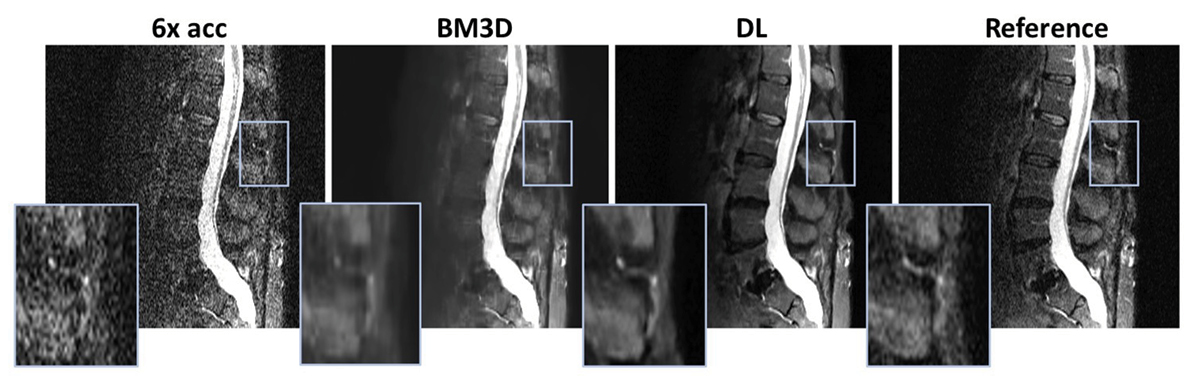

Leveraging artificial intelligence, Yang aims to enhance quality and reduce scan times. Preliminary results show promising outcomes, with some scans reduced by 50-73%. “The ideal future is a full stack of AI tools, from acquisition to image reconstruction, enhancement, post-processing, contour drawing, and reporting,” Yang said.